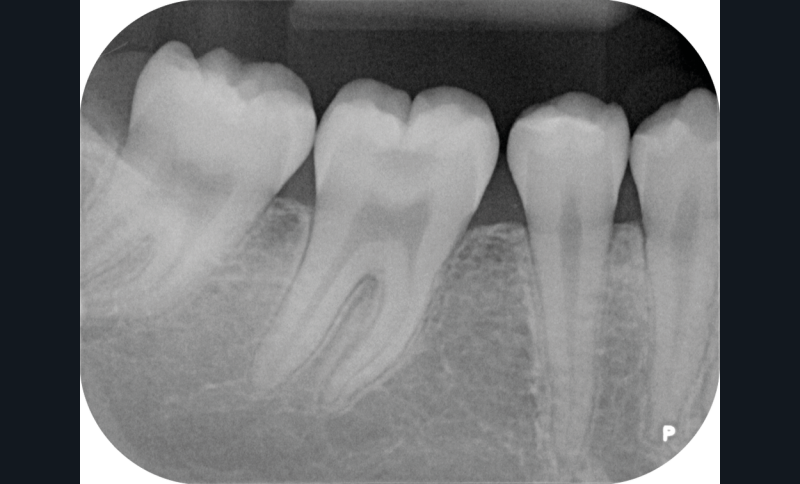

Nous détaillons la technique à travers le cas d’une jeune fille de 18 ans présentant des lésions carieuses sur quatre dents (fig. 1 à 14).

Il est tout à fait possible d’utiliser cette technique lorsque la cavité a atteint une paroi proximale. Il suffit alors de recréer d’abord le mur proximal manquant en résine composite, puis d’ajuster le tampon pour qu’il n’interfère pas avec ce dernier. La cavité de classe II se transforme alors en cavité de classe I [7].